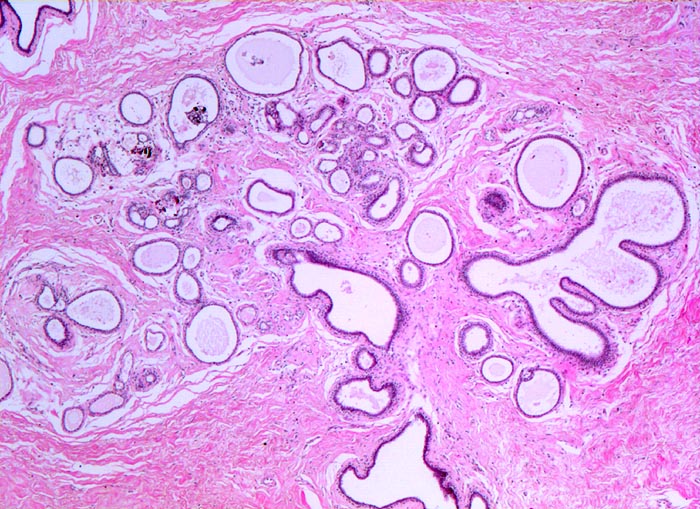

• Ausgeprägte Fibrose und zystisch erweiterte Gangstrukturen in organoider Anordnung.

• Rundlicher blauvioletter Mikrokalk in den Azini benigner Drüsenläppchen.

• Kolumnarzellveränderung: erweiterte Drüsen ausgekleidet von hochprismatischem Epithel mit apikalen Nasen (snouts) gefüllt mit Sekret und teilweise assoziiert mit Mikrokalk.

• Im Zentrum des Präparates stark erweiterte Gänge mit intraduktalen peripheren Papillomen.